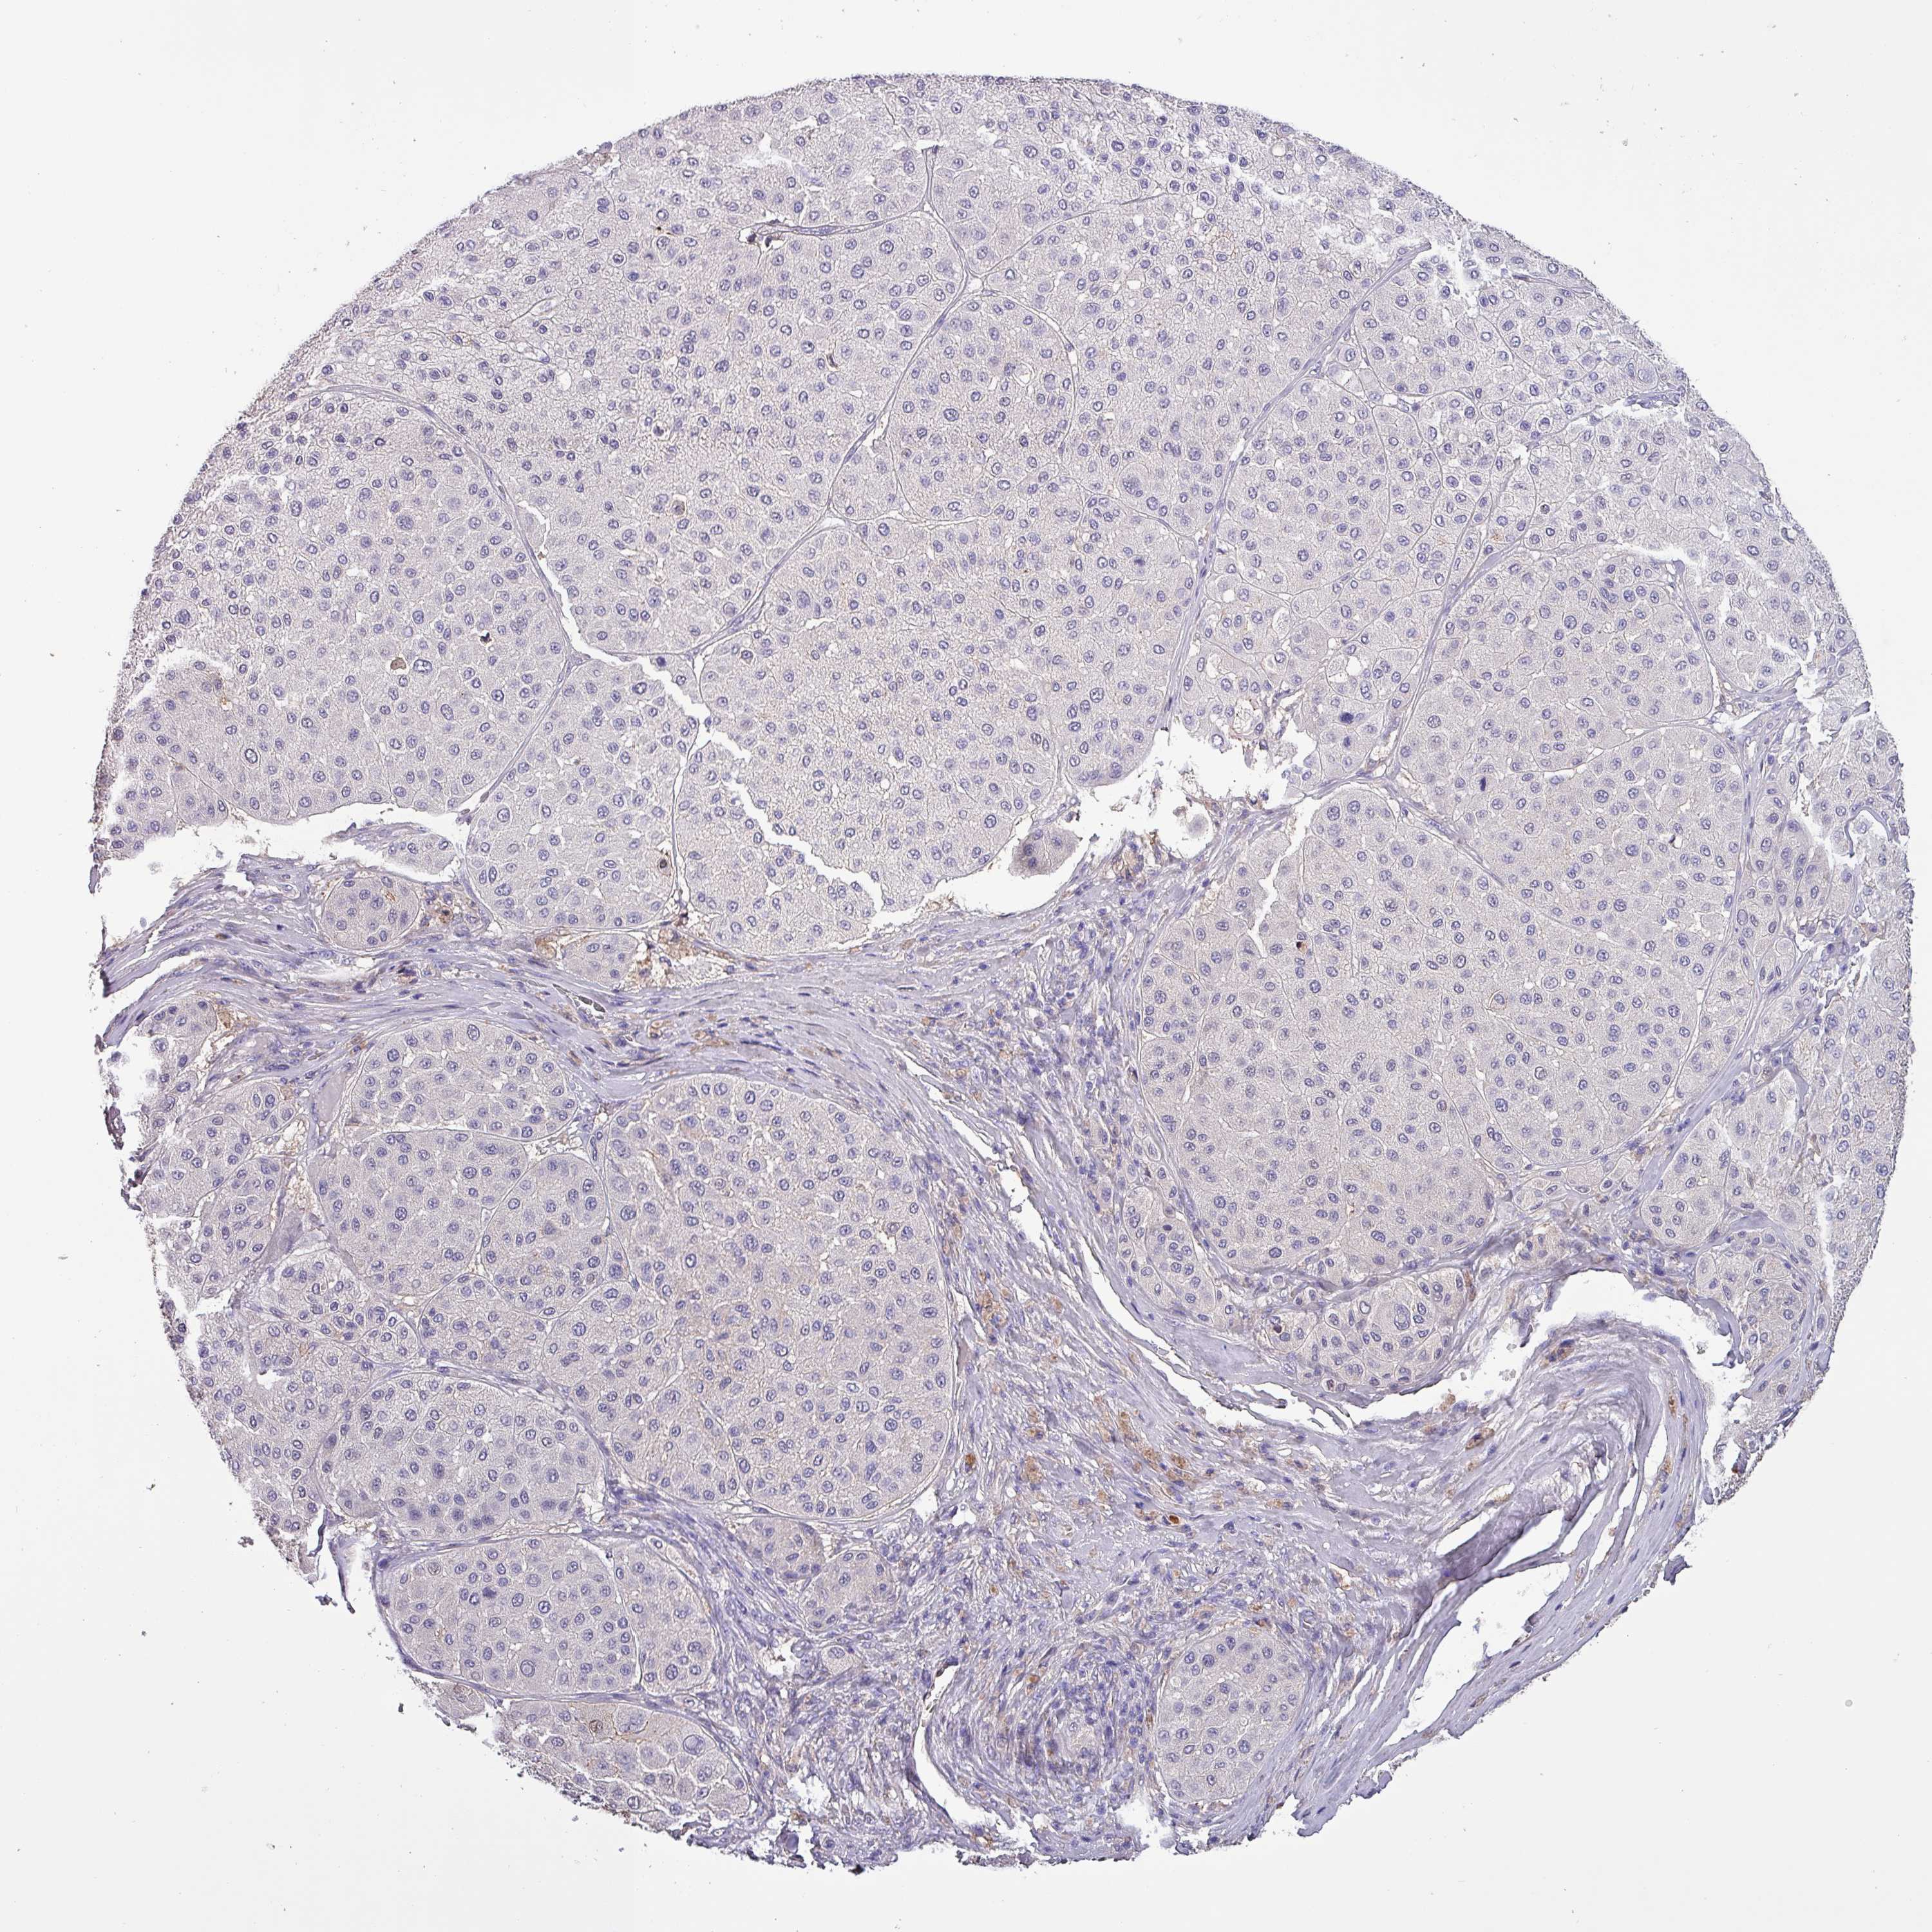

MELANOMA - Protein expressioni

A mouse-over function shows sample information and annotation data. Click on an image to view it in a full screen mode. Samples can be filtered based on level of antibody staining by selecting one or several of the following categories: high, medium, low and not detected. The assay and annotation is described here.

Note that samples used for immunohistochemistry by the Human Protein Atlas do not correspond to samples in the TCGA dataset.

Antibody stainingi

Antibody staining in the annotated cell types in the current human tissue is reported as not detected, low, medium, or high, based on conventional immunohistochemistry profiling in selected tissues. This score is based on the combination of the staining intensity and fraction of stained cells.

Each image is clickable and will lead to virtual microscopy that enables deeper exploration of all samples and also displays staining intensity scores, fraction scores and subcellular localization as well as patient and tissue information for each sample.

Antibody HPA045402

Staining

High

Medium

Low

Not detected

Intensity

Strong

Moderate

Weak

Negative

Quantity

>75%

75%-25%

<25%

None

Location

Nuclear

Cytoplasmic/membranous

Cytoplasmic/membranous,nuclear

Malignant melanoma, NOS

Malignant melanoma, Metastatic site